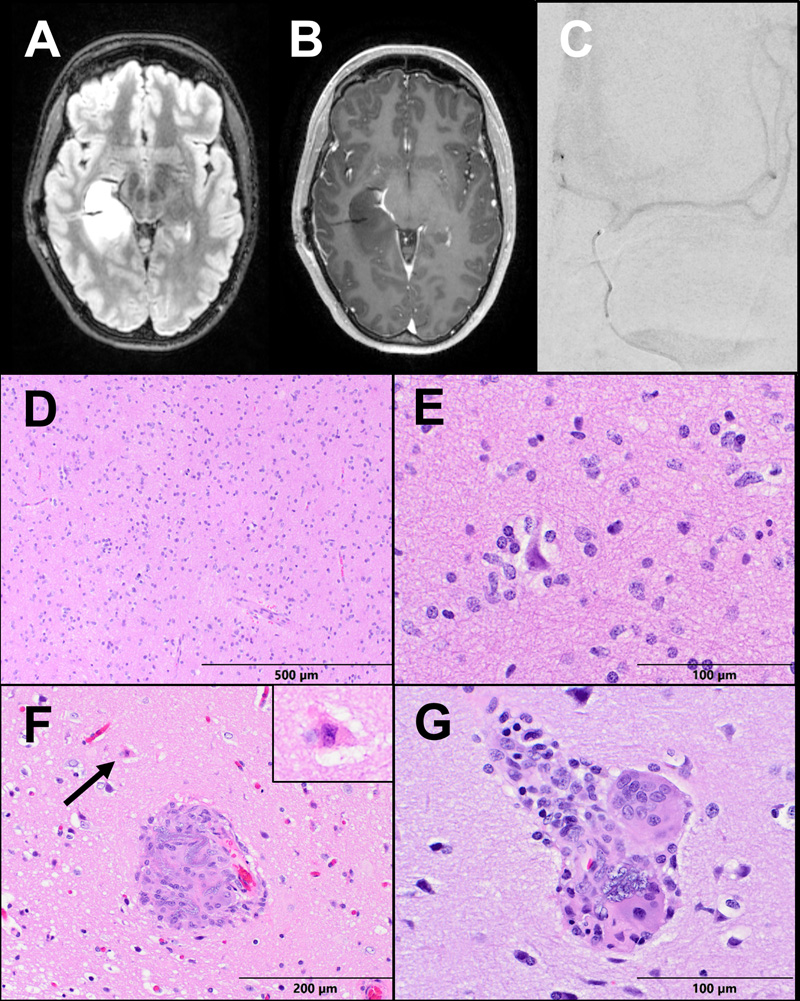

A 55-year-old right-handed man presented with new-onset generalized tonic-clonic seizures. Magnetic resonance imaging (MRI) revealed a non-enhancing infiltrative and expansile T2-hyperintense mass centered within the right superior temporal gyrus (Fig. 1a-b). The patient underwent bilateral Wada testing. Vascular access was obtained via the right femoral artery using the modified Seldinger technique. A 5-French angled glide diagnostic catheter was introduced over a 0.035 Terumo Glidewire into the descending thoracic aorta and then the cervical internal carotid artery under direct fluoroscopic visualization. A Codman Prowler Select Plus infusion microcatheter with a Synchro 2 microwire was used to catheterize the internal carotid artery just distal to the posterior communicating artery. An angiographic run was performed to confirm catheter position prior to Brevital (methohexitol) infusion (Fig. 1c). The Wada test demonstrated clear left hemisphere language dominance and greater left hemisphere memory support.

Figure 1: Case 1 Imaging and Pathology. (A) Axial T2-FLAIR and (B) T1 post-contrast sequences of a brain MRI demonstrating a non-enhancing infiltrative and expansile T2-hyperintense mass centered within the right superior temporal gyrus. (C) A PA view of digital subtraction angiogram demonstrating a microcatheter within the right internal carotid artery. (D-E) The tumor resection demonstrates a moderately to highly cellular infiltrating glioma, with significant nuclear atypia and scattered mitoses (arrow). (F-G) Parenchymal vessels within the resection display giant cell vasculitis and contain basophilic granular foreign material consistent with hydrophilic polymer.

Pathology:

Evaluation of the primary resection specimen revealed a moderately to highly cellular diffusely infiltrating glioma. There was significant pleomorphism and focally frequent mitoses, but no microvascular proliferation or necrosis, meeting histologic criteria for anaplastic astrocytoma, WHO Grade III (Fig. 1d-e). Molecular analysis by next-generation sequencing (NGS) and microarray revealed features of primary IDH-wildtype glioblastoma, including EGFR amplification, and the tumor was upgraded to WHO Grade IV.5 Additionally noted on pathologic examination were scattered foci of giant cell vasculitis and intravascular foreign material. The foreign material was granular, blue-gray and non-polarizable, morphologically consistent with hydrophilic polymer material. No surrounding ischemic changes were identified (Fig. 1f-g).